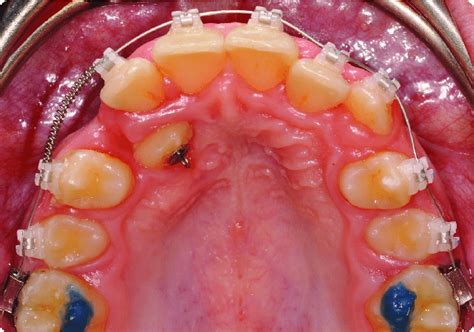

- Marzo de 2005: retiramos el aparato de Herbst y, debido a la falta de contactos oclusales estables, tomamos una impresión para un aparato funcional miostático, de uso nocturno y compatible con la aparatología fija multibrackets (fig. 9 A, B). Este aparato lleva un resorte tipo Coffin y acrílico oclusal sólo a nivel de los segundos molares, a los que se sujeta a través del diseño de ganchos de Dominique Groberty para la sujeción a las bandas (fig. 10).

Figura 9 A) Vista intraoral, inmediatamente después de colocar aparatología fija multibrackets, tras retirar el aparato de Herbst. B) Vista intraoral a las 48 h con el aparato funcional nocturno de contención colocado.

Figura 10. Diseño del aparato funcional de contención nocturno.

Cementamos aparatología fija multibrackets en ambas arcadas, con slot de .018" ´ .025" y la prescripción de Bench. Comenzaremos a nivelar las arcadas con arcos continuos primero, y luego con arcos de curva de Spee reversa en la arcada inferior y elásticos intermaxilares.